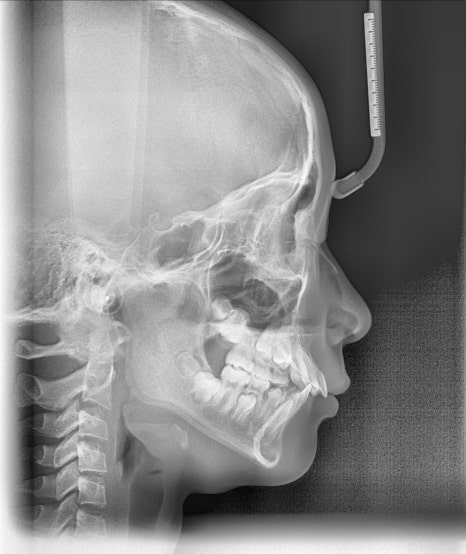

치료 전후 악골의 위치 변화

치료 결과 하악골은 전방성장하였으며, 과개교합도 많이 개선되었습니다. 헤드기어로 상악골의 성장도 억제되어 돌출되었던 위 앞니 각도도 개선되었고, 위-아래 앞니 사이 간격이 많이 줄었습니다. 위 앞니에 눌려 돌출되었던 하순도 개선되어 straight profile이 완성되었습니다.

액티베이터 치료 전후 옆얼굴 변화